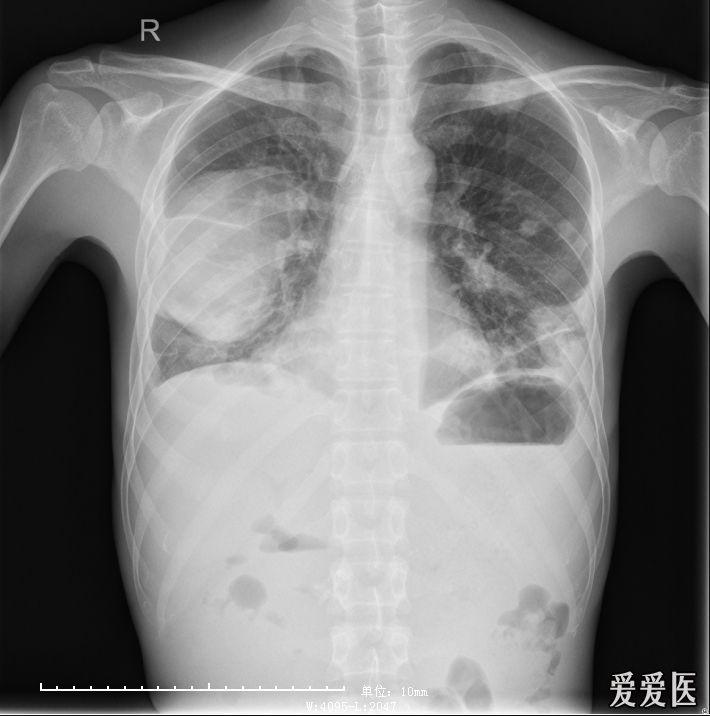

【影像读片】肺脓肿合并脓胸?

左侧脓胸病例分享

肺脓肿